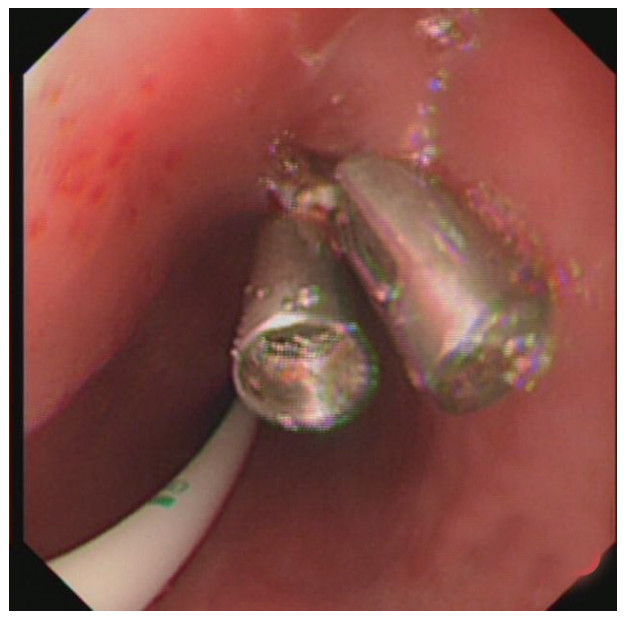

治疗经过:急诊予美罗培南0.5 g,1次/12 h抗感染,补液支持,心包引流等治疗措施,收住感染科后继续抗感染治疗,期间心包积液培养出白假丝酵母菌,加用氟康唑200 mg,1次/d, 口服,心包积液、左侧胸腔积液引流等措施,治疗10 d后复查胸部CT仍有中大量心包积液伴少许积气,纵隔积气;左侧少量胸腔积液,两肺叶间裂少许积液。对照前片(2020.10.26)心包积气及左侧胸前积液有增多,叶间裂积液新发,心包积液略有减少。右肺下叶感染,左肺下叶膨胀不全,较前右肺下叶感染有吸收,左肺下叶膨胀不全新发。考虑不能排除食管纵隔瘘,予口服碘海醇后胸部CT检查(图 3~6):约胸6椎体水平食管纵隔瘘,瘘口为相应水平食管壁右前方可能;胃镜(图 7):食道距门齿25 cm右后壁见一直径约1.0 cm凹陷,内有一小瘘口。胃镜下予钛夹2枚夹闭瘘口(图 8),同时植入空肠营养管。至此患者病情明确诊断食管心包瘘,患者经以上治疗后心包积液、胸腔积液逐渐减少,于11月13日拔除心包及胸腔引流管,因患者签字回当地就诊,予口服莫西沙星、氟康唑带药出院,出院后随访,患者未回当地医院治疗,仅在家中继续空肠营养管饲喂及口服抗菌药物治疗。

图 8 瘘口已予2枚钛夹夹闭